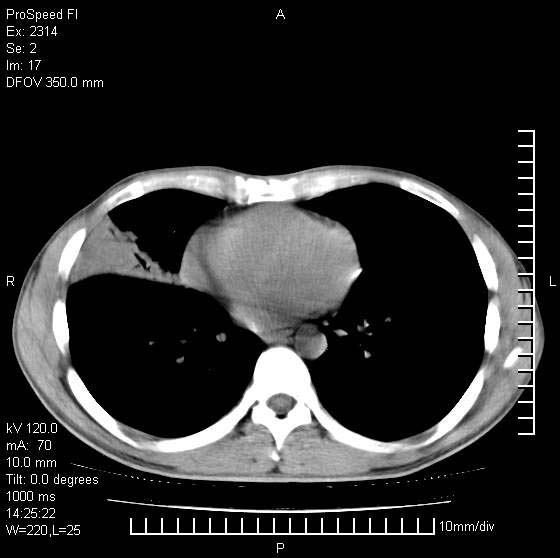

男性,再生障碍性贫血,入院前发热10天,最高40c,右侧胸痛,外院ct示右上,中肺边缘模糊的球性影(就是我现在图中标示的范围),考虑炎症,在我院使用头孢呋辛,洛美沙星10天,高烧消退,自感下午稍有发热,但今天ct示右上,中肺病灶明显扩大,还是考虑炎症,看其中的球型影是否霉菌感染??,是否能排除结核?

右肺中叶外侧段病变,上缘界限不清,下缘锐利,以段性发病为主,内见巨大空洞及空洞内容物,结合病史首先考虑:化脓性肺炎。不除外霉菌感染!

考虑霉菌感染.理由1\\有临床基础疾病,2\\有坏死的空腔,其内可见软组织影.

片状高密度影内见空洞影,内可见球形软组织密度影,并有新月征,考虑霉菌感染.